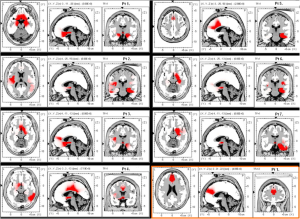

Evidence from published research suggests CES use activates particular groups of nerve cells that produce the neurotransmitters serotonin and acetylcholine which can affect the chemical activity of nerve cells that are both nearby and distant in the nervous system. By changing the electrical and chemical activity of certain nerve cells, CES devices like Alpha-Stim® (seen on the left) appear to amplify activity in some neurological systems and deactivate activity in others. This neurological ‘fine tuning’ occurs either as a result of, or together with the production of a certain type of electrical activity pattern in the brain known as an alpha state. CES has been found increase alpha and decrease delta, theta, and beta waves on qEEG brain maps. This typically results in feeling calm, relaxed and focused. This appears to decrease stress effects, reduce agitation, stabilize mood, and regulate both sensations and perceptions of particular types of pain.

Adapted from Alpha-Stim.com